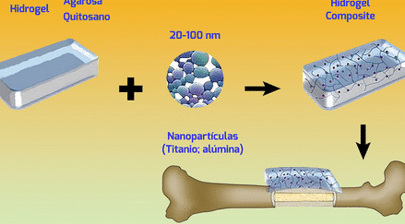

La medicina regenerativa ha encontrado en el uso de hidrogeles inteligentes en la regeneración ósea una alternativa...